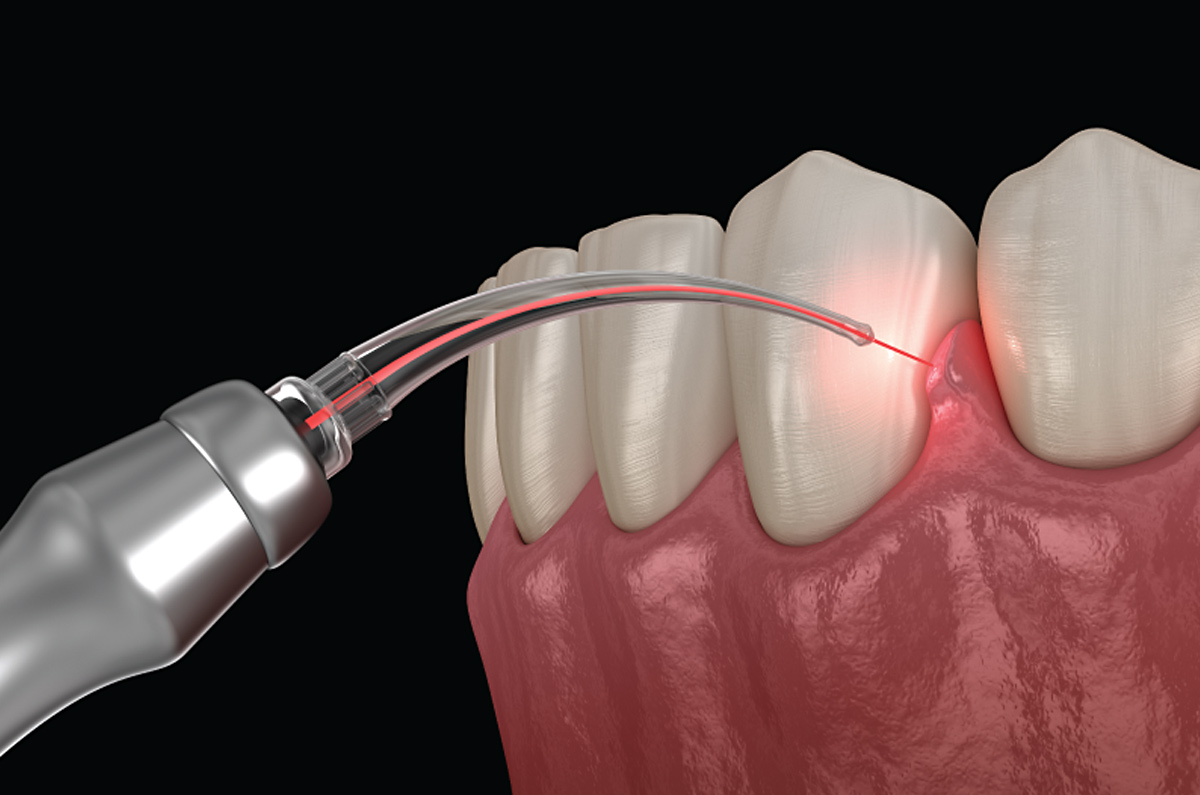

Amor Dental by Dr. Lorna M. Quimco offers premier dental services at affordable rates, including veneers, bridges, whitening, implants, TMJ therapy, braces, and dentures. Established in 1999, our goal is to provide top-notch dental care for confident smiles. Dr. Quimco, with over 25 years of experience, is renowned for her expertise in cosmetic dentistry. She graduated from Cebu Doctors University and pursued postgraduate studies at the Philippine Academy of Esthetic Dentistry, excelling in Dental Implantology under Dr. Hom-Lay Wang at the University of Michigan.

She practices Biomimetic Dentistry, focusing on preserving tooth structure by replicating natural tissues. She also specializes in Neuro-Muscular Dentistry, employing advanced techniques for personalized treatment plans. Committed to continuous learning, she travels globally for the latest innovations.